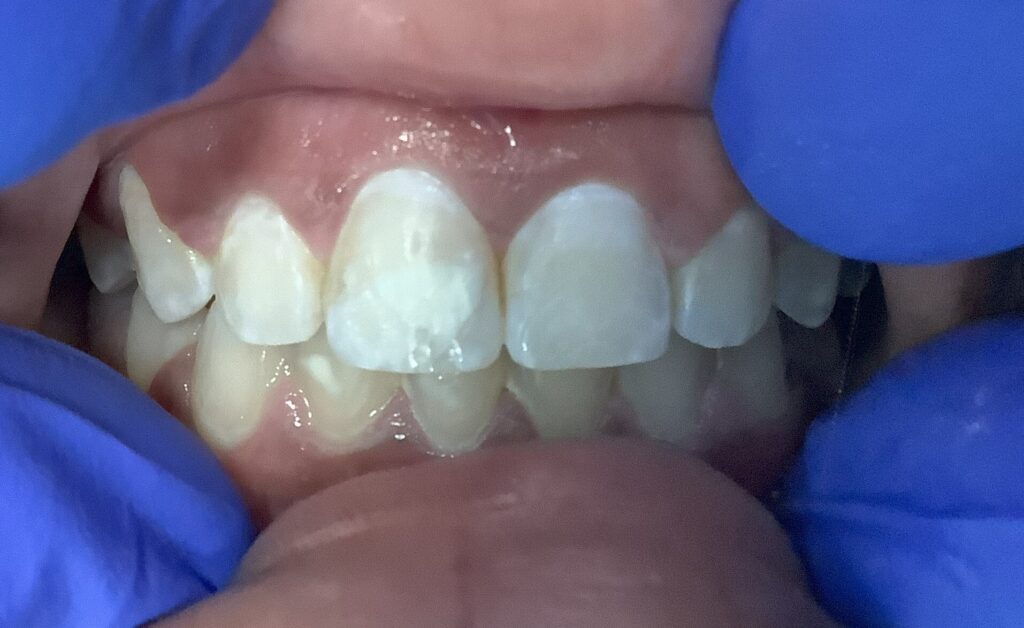

White Spot Removal Results

teeth showing the aftermath of dental work